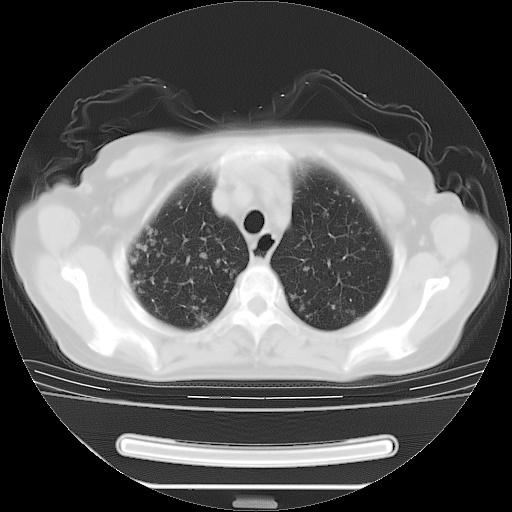

ct示两肺粟粒状病灶,以两肺上叶尖后段及下叶背段分布为主;首先考虑结核。请战友们分析。

考虑 1 弥漫性泛细支气管炎, 2 结核不除外/.  有小叶中心结节 和 树芽征!!

两肺内病灶呈小结节状和树芽状,纵膈的肿大的淋巴结密度不均匀,并见有钙化,考虑为两肺结核可能更大些。

两肺内病灶呈小结节状和树芽状,纵膈的肿大的淋巴结密度不均匀,并见有钙化,多形态病灶,考虑为两肺结核,肝内考虑小囊肿。